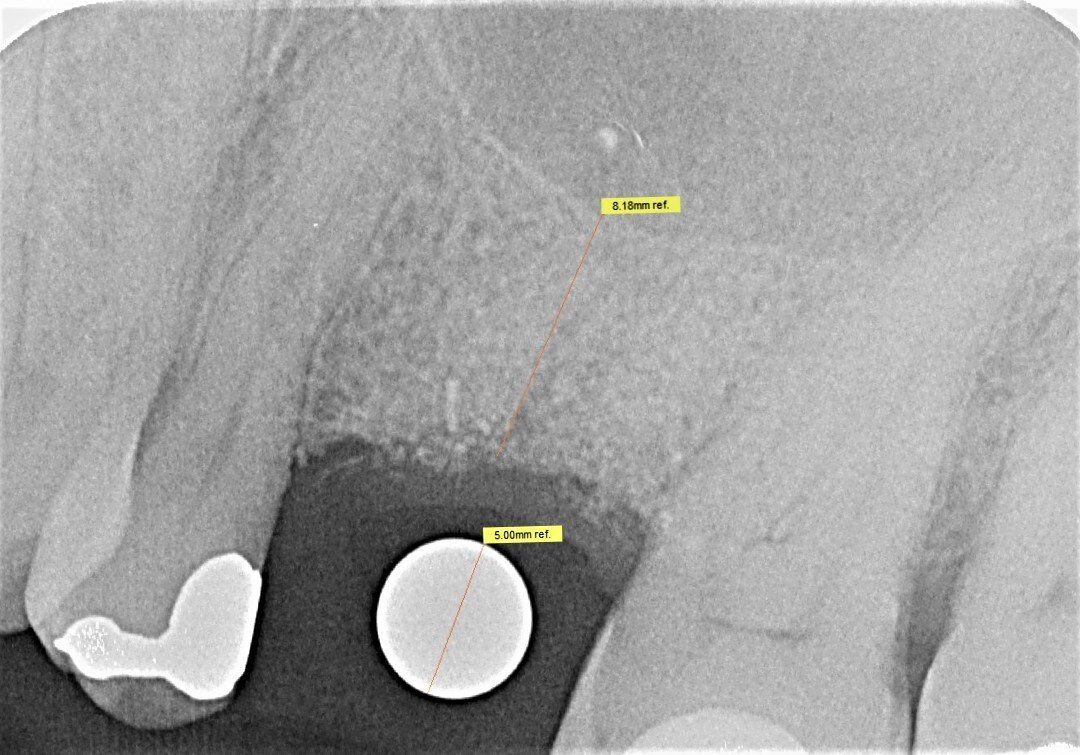

Durch den Verlust des Zahnes wandelt sich der Kieferknochen um. Nach der oberflächlichen Heilung wird das knöcherne Zahnfach vom Körper rasch abgebaut. Knochen ist für den Körper ein "teures" Gewebe, und ohne die funktionelle Kaubelastung durch einen Zahn gibt es für den Körper keinen Grund mehr, das knöcherne Zahnfach zu erhalten. Allein im ersten Jahr nach der Zahnentfernung gehen 50% des umgebenden Knochens verloren! Das ist insbesondere dann von Nachteil, wenn geplant ist, später ein Implantat für den Ersatz des Zahnes zu setzen. Ohne kiefererhaltende Maßnahmen reicht oftmals der nach der Heilung verbliebene Knochen nicht mehr aus, ein hinreichend großes Implantat einzusetzen bzw. dieses auch ideal zu positionieren.

Aus diesem Grund werden seit vielen Jahren

Knochenersatzmaterialien aus tierischem, pflanzlichen oder mineralischen Ursprung verwendet, um die Schrumpfung des Kieferknochens aufzuhalten und dadurch die ursprünglichen Dimensionen zu bewahren.